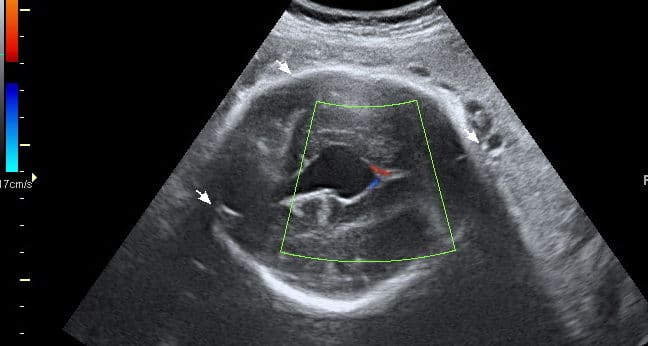

Ultrassom Cisto e Plexo Coróide

Cisto de Plexo Coróide

As imagens ultra-sonográficas dos plexos coróides consistem em estruturas hiperecogênicas, intra-ventriculares ao nível do corpo, trígono e corno inferior. A presença de estrutura cística no…